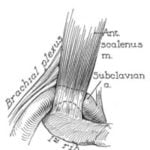

1861

Holmes Coote

Holmes Coote performed the first TOS surgery. A 26 year-old female servant described a hard mass in her left lower neck, present since childhood. The “tumor” had grown recently, and she experienced paresthesias in the tips of her fingers, with loss of pulses at the wrist, wasting of muscles in the arm, and weakness leading to dropping of items. Mr. Coote explored the area while the patient was “fully under the influence of chloroform.” He noted a bony ‘tumor,’ which he had to divide from the cervical vertebra. He also found it was attached to the first rib anteriorly. He removed as much of the ‘tumor’ as he could, and pulses returned in the left upper extremity. Coote described his trepidation at exploring this area thusly: “But the region was not a pleasant one for any proceeding demanding the use of the knife. The subclavian artery and vein were in front; the axillary plexus of nerves lay spread out above; below, the apex of the lung, covered by the pleura, rose up in dangerous proximity; on the scalenus was the phrenic nerve; while towards the mesial line were the important vessels and nerves passing to the head, together with the vertebral vessels and thoracic duct. You can understand, therefore, why I was cautious in what I did.” The bony tumor was referred to as “an exostotic growth from the transverse process of the seventh cervical vertebra,” and “a development of the costal element, the rib, of the seventh cervical vertebra.” Thus, Coote became the first person to surgically treat a TOS patient.